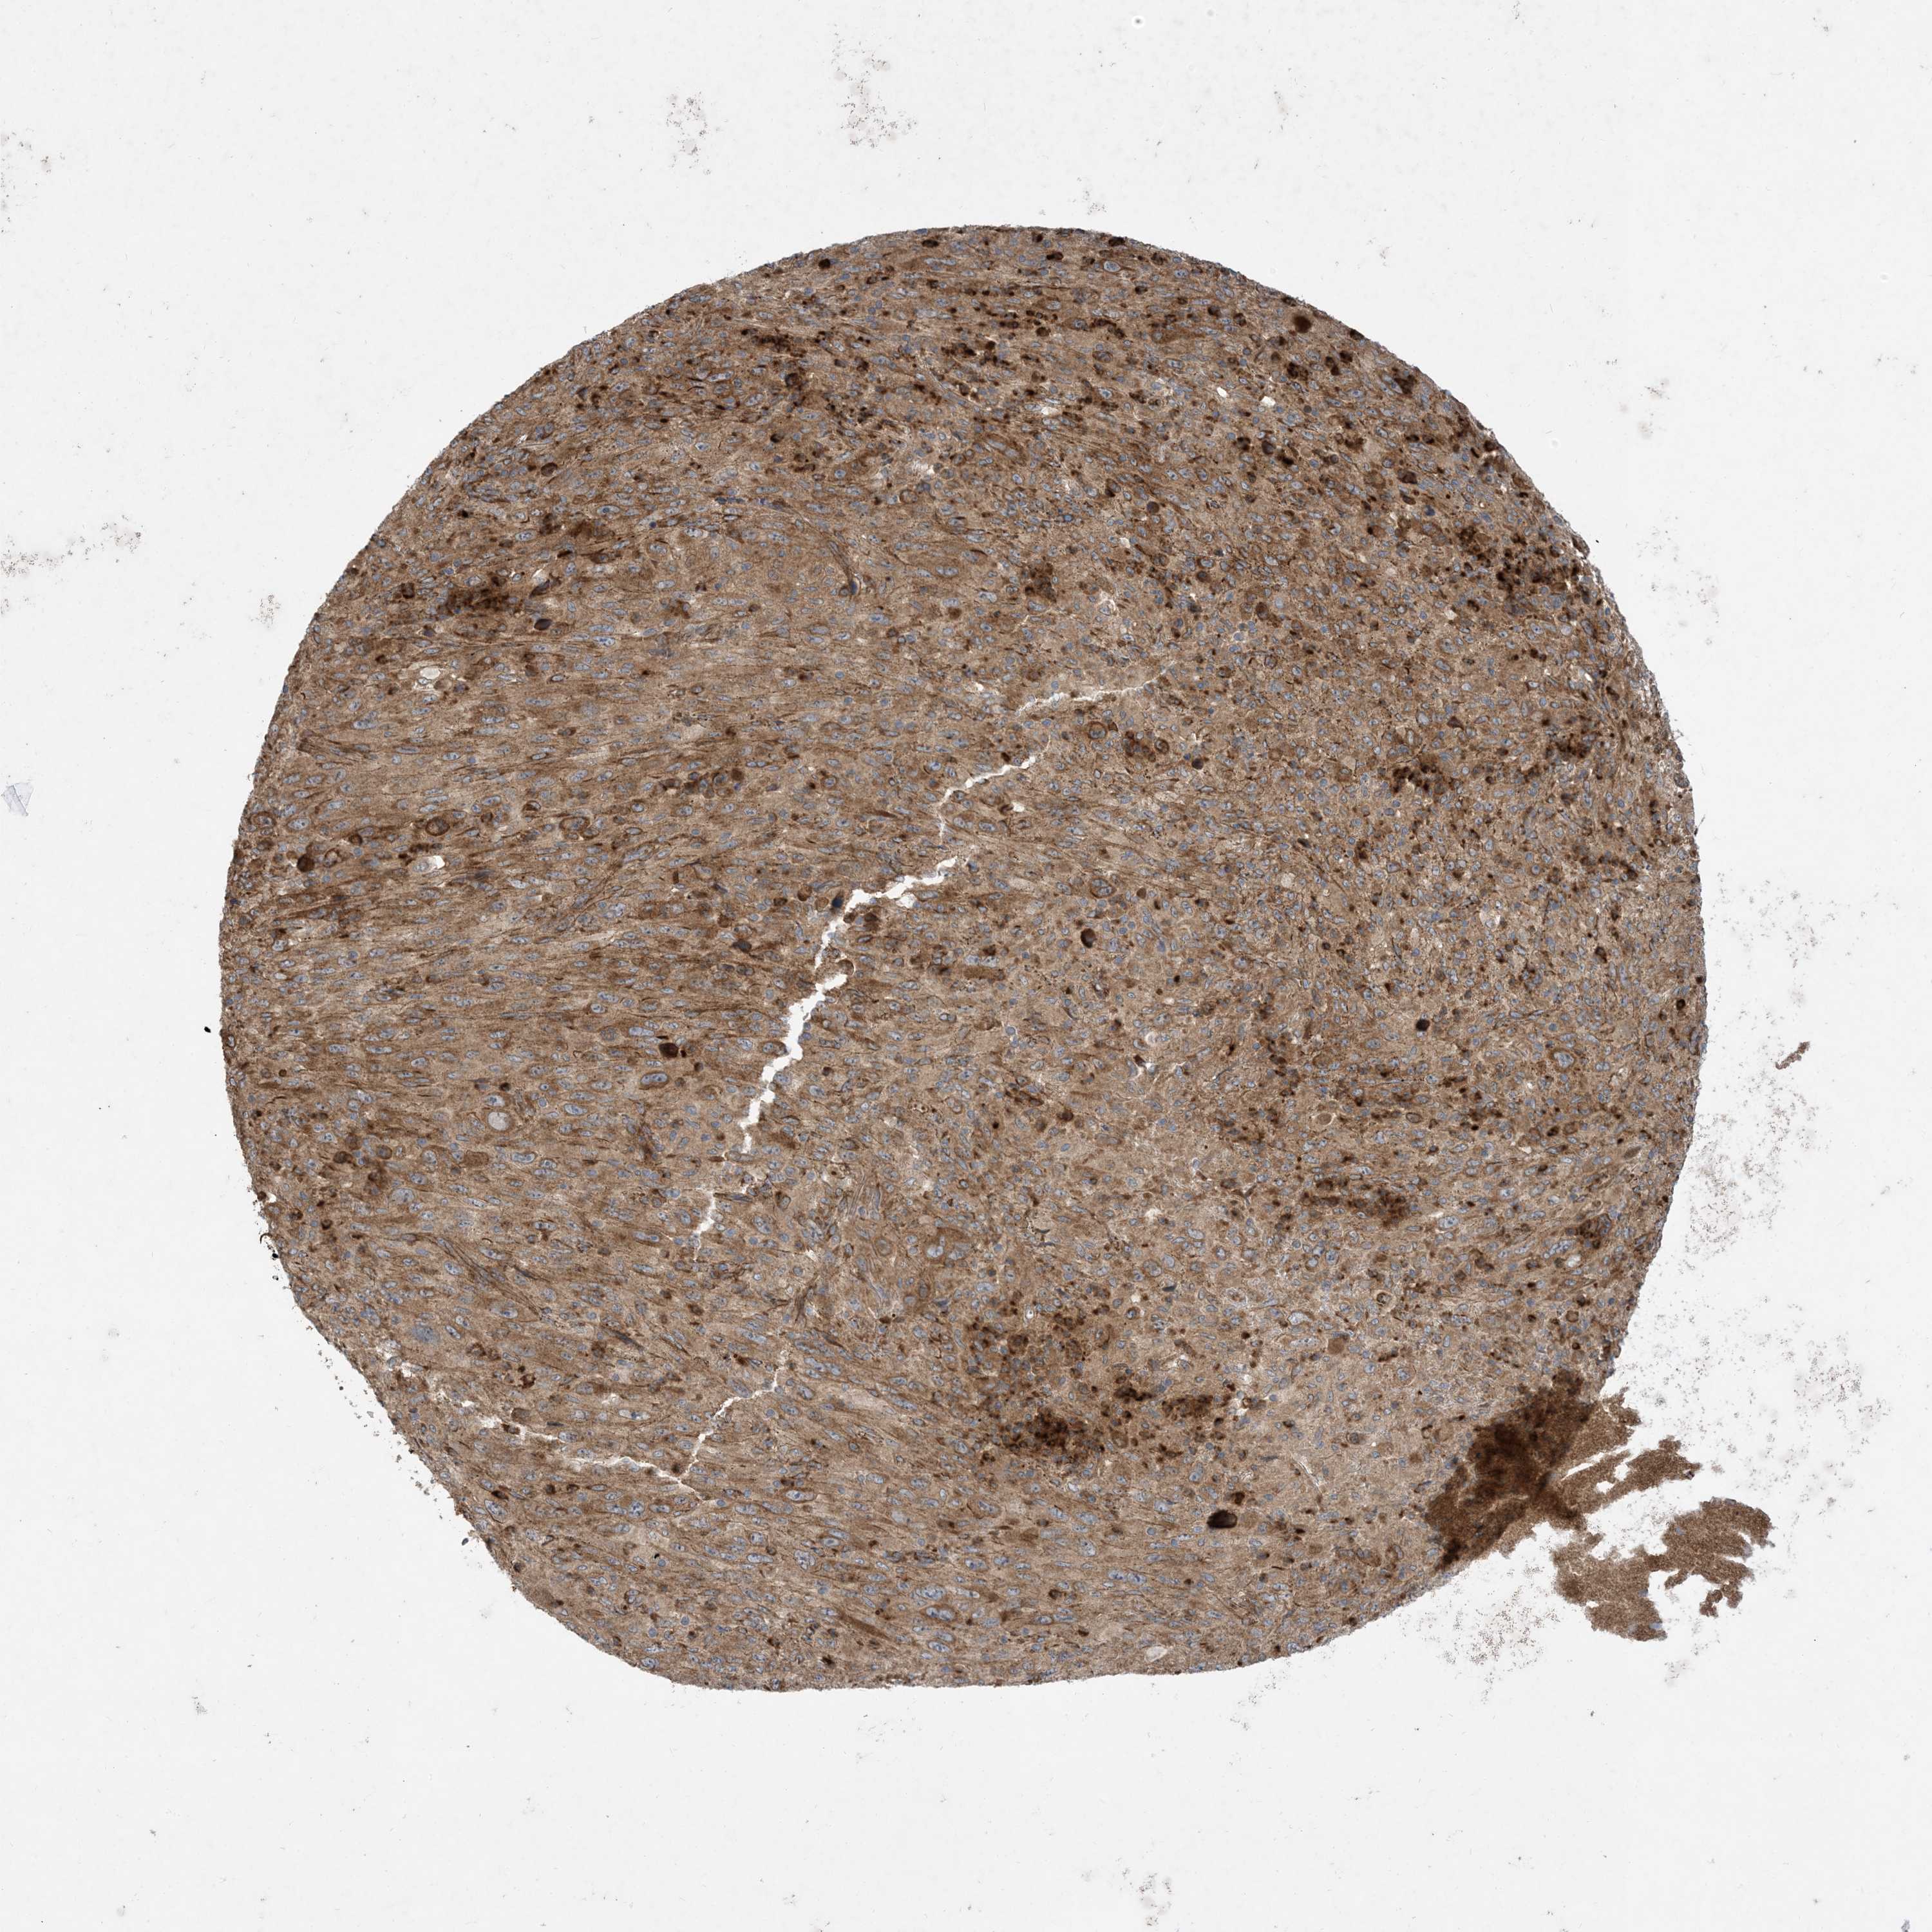

MELANOMA - Protein expressioni

A mouse-over function shows sample information and annotation data. Click on an image to view it in a full screen mode. Samples can be filtered based on level of antibody staining by selecting one or several of the following categories: high, medium, low and not detected. The assay and annotation is described here.

Note that samples used for immunohistochemistry by the Human Protein Atlas do not correspond to samples in the TCGA dataset.

Antibody stainingi

Antibody staining in the annotated cell types in the current human tissue is reported as not detected, low, medium, or high, based on conventional immunohistochemistry profiling in selected tissues. This score is based on the combination of the staining intensity and fraction of stained cells.

Each image is clickable and will lead to virtual microscopy that enables deeper exploration of all samples and also displays staining intensity scores, fraction scores and subcellular localization as well as patient and tissue information for each sample.

Antibody HPA035599

Staining

High

Medium

Low

Not detected

Intensity

Strong

Moderate

Weak

Negative

Quantity

>75%

75%-25%

<25%

None

Location

Nuclear

Cytoplasmic/membranous

Cytoplasmic/membranous,nuclear

Malignant melanoma, NOS

Malignant melanoma, Metastatic site